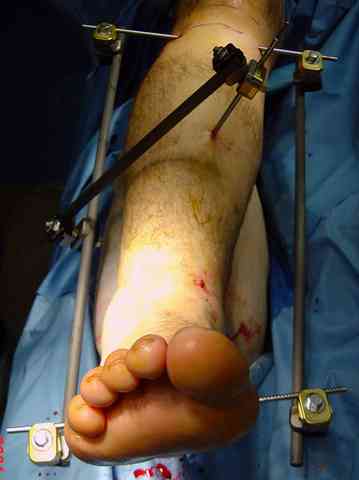

Снова приветствую вас, коллеги. К моменту вступления в обсуждение аксакалов, операция была, увы, выполнена(31.10.07.) Начали с доступа к наружной лодыжке, произвели ее фиксацию спицами, развернули кусок заднего края, наложили дистрактор, затем произвели дистракцию, фиксацию спицами дистального эпиметафиза б/бк,Рентгено-контроль. синтез наружной лодыжки 1/3пластиной. из двух коротких разрезов сформирован канал под медиальную тибиальную пластину LCP. Края ран ушиты без натяжения. Прочувствовать жесткость фиксации винтами с угловой стабильностью не удалось, поэтому дистрактор оставлен на энное время.

На представленных R-снимках не окончательный вид после остеосинтеза. Дистальная опора давила на стопу, пришлось ее сместить проксимально, в рез-те чего, она закрыла щель сустава, последние снимки не информативны.

2. Второе. Следует обязательно усилить фиксацию: спицы через передний отдел стопы и пяточную кость, вторая спица через проксимальное кольцо и 1-2 стержня в проксимальный отломок б/б кости. Сроки фиксации до 8 недель. Аппаратом можно устранить, кажется, появившийся вальгус. В подобных ситуациях лучше ведут себя стержни, которыми можно сопоставить и сдавить лодыжки и задний край б/б кости. Привожу случай восстановления голеностопного сустава спустя 2,5 мес.(этап лечения) после травмы со стержнями.

3. Дистальную опору можно было бы взять в виде ¾ кольца или двух разноуровневых полуколец, соединенных небольшими стяжными стержнями. ¾ кольца - не давят на стопу, а разноуровневые полукольца «обходят» сустав. Одно снизу, другое сверху.